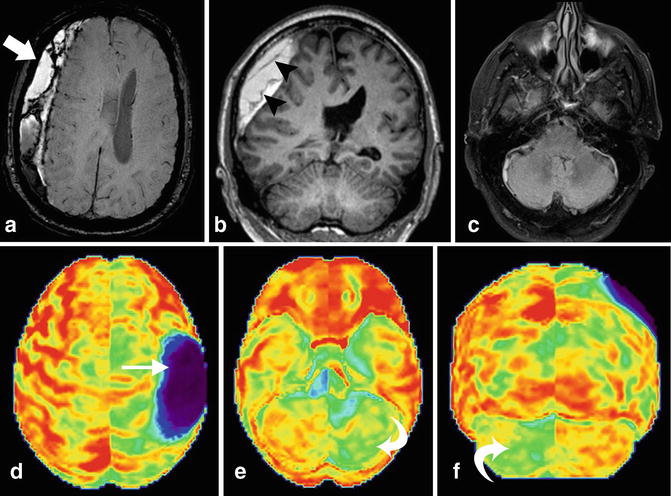

Figure 1 Crossed Cerebellar Diaschisis As An Indicator Of Severe Cerebral Hyperperfusion After Direct Bypass For Moyamoya Disease Springerlink

Crossed Cerebellar Diaschisis Radiology Case Radiopaedia Org

Crossed Cerebellar Diaschisis Radiology Reference Article Radiopaedia Org

Crossed Cerebellar Diaschisis Springerlink